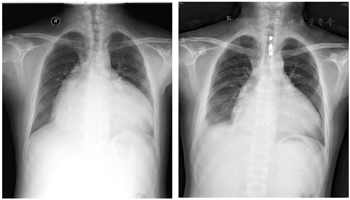

入院后完善检验提示三大常规、凝血六项、肾功能、血气分析、心肌损伤标志物及BNP正常。而肝功能检验提示:ALP、GGT、TBil等显著增高,提示肝功能异常。胸部X片提示:心界明显扩大,心胸比约为0.81(图1)。心电图提示:心房颤动;电轴右偏;完全性右束支阻滞;心脏顺钟向转位;T波改变窦性心律,T波低平(图2)。进一步完善心脏彩超:左心房32 mm、左心室40 mm;右心房横径100 mm、上下径106 mm;右心室前后径65 mm、横径81 mm、上下径62 mm;肺动脉主干24 mm,右室流出道60 mm;右心室EF 34%;左心室EF 66%,室壁未见节段性运动异常;三尖瓣:瓣环52 mm,关闭时瓣口对合差,反流面积37 cm2,流速190 cm/s,压差15 mmHg(图3)。腹部彩超:肝脏:右叶斜径16 mm,肝段面增大,肝静脉明显增宽(右支2.4 mm,中支2.2 mm,左支2.0 mm);下腔静脉内径4.0 mm;胆囊壁粗糙增厚;胰、脾及双肾未见异常。

手术前后彩超对比提示右心显著缩小,提示治疗后患者右心结构得到恢复。手术前后胸部X片对比提示心影缩小,心胸比从0.81下降到0.72。结合患者心功能、后期复查结果,提示冠脉重建后右心心肌血供恢复,心肌重塑,大小恢复。术后3个月复查心电图:阵发性房性心动过速(房室传导比例呈2:1传导);电轴右偏;完全性右束支传导阻滞;ST-T改变。通过治疗患者右心大小逐渐恢复正常,心功能恢复,日常生活无明显受限,规律服药、定期复查中,对治疗效果满意。